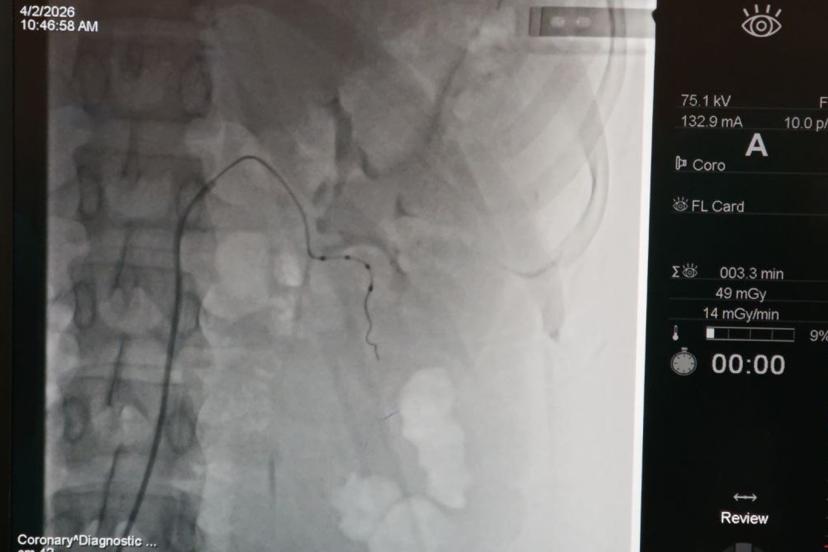

İnönü Üniversitesi Turgut Özal Tıp Merkezi'nde Kardiyoloji Uzmanı Prof. Dr. Hasan Pekdemir tarafından gerçekleştirilen renal arter denervasyonu işlemiyle, ilaç tedavisine yanıt vermeyen genç hastanın tansiyonu kontrol altına alındı. Bölge için ilk olan uygulama, dirençli hipertansiyon hastalarına umut oldu.

İnönü Üniversitesi Turgut Özal Tıp Merkezi Kardiyoloji Anabilim Dalı Öğretim Üyesi Prof. Dr. Hasan Pekdemir ve ekibi tarafından gerçekleştirilen başarılı renal arter denervasyonu işlemiyle hasta sağlığına kavuştu.

Bölgede bir ilk ve Malatya'da ilk kez gerçekleştirilen işlem hakkında İLKHA muhabirine konuşan Prof. Dr. Hasan Pekdemir, uygulamanın gebelik planı bulunan ancak tedavisinin bunu sınırlandırdığı genç bir hastaya başarıyla yapıldığını ve tansiyon değerlerinin kontrol altına alındığını ifade etti.

Bu noktada devreye giren renal arter denervasyonu yönteminin, böbrek damarlarının etrafındaki sempatik sinirlerin ablasyon yöntemiyle etkisiz hale getirilmesine dayandığını belirten Pekdemir, yöntemin etkisini şu sözlerle anlattı:

"Bu sinirleri yaktığımızda tansiyonu yükselten sinyallerin beyne iletilmesi engelleniyor. Böbreğe giden yanlış uyarılar ortadan kalkıyor. Bunun sonucunda damarlar genişliyor, tuz ve su tutulumu azalıyor ve hastanın tansiyonunda ciddi düşüşler sağlanıyor."